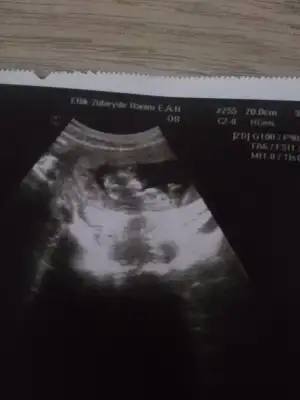

bana 12. hafta kız demiştiniz, bugün doktorda kesin olarak kız dedi :)